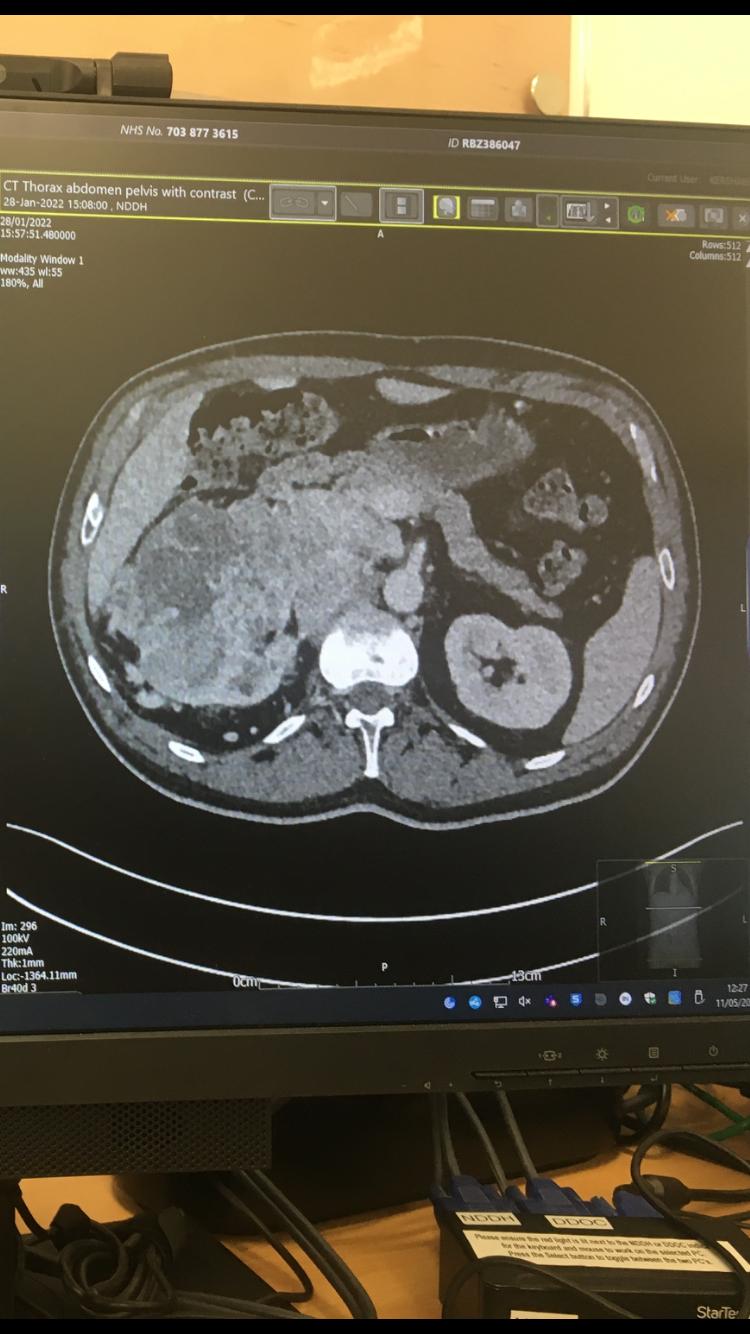

Above: Scans showed Jarlath had a huge tumour wrapped around his spine and kidney – at the time doctors gave him just weeks to live.

After his friend insisting on him seeing a doctor, he was sent for a routine X-ray but was immediately hospitalised and diagnosed with extensive lung tumours and a 15.5-centimetre tumour around his spine and kidney, with an initial prognosis of six to eight weeks to live.

Above: Initial scans showed multiple tumours in his lungs and a large one around his spine and kidney.

Over the years of treatments, the medical professionals described him as a ‘super responder’, with significant kidney tumour reduction from 15.5cm to 4.5cm and cleared lung tumours.